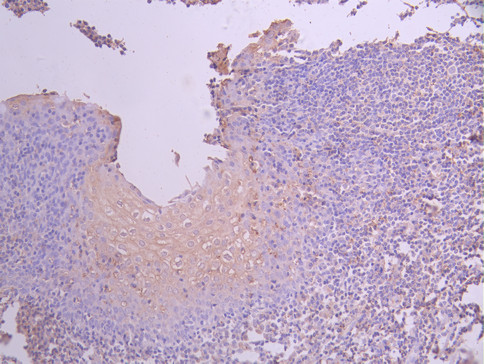

• IHC image of CSB-RA004929MA3HU diluted at 1:50 and staining in paraffin-embedded human prostate cancer performed on a Leica BondTM system. After dewaxing and hydration, antigen retrieval was mediated by high pressure in a citrate buffer (pH 6.0). Section was blocked with 10% normal goat serum 30min at RT. Then primary antibody (1% BSA) was incubated at 4°C overnight. The primary is detected by a Anti-Human lgG, Fcy Fragment Specific labeled by HRP and visualized using 0.05% DAB.